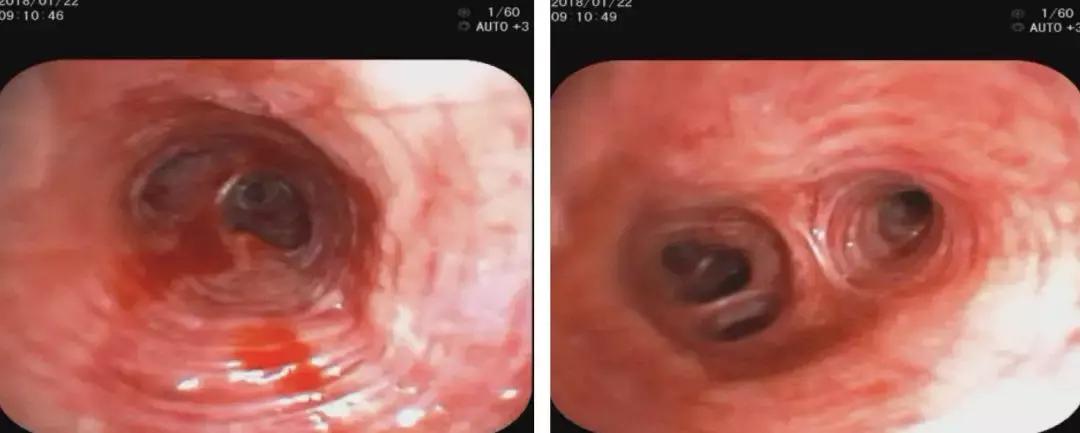

2018-01-22行支气管镜检查:示两侧支气管粘膜充血明显,可见少量白色分泌物,充分吸引;于左下叶生理盐水20ml灌洗2次,回吸收均约10余ml;左上叶、左下叶刷检,刷片共6张。(气管镜报告如下图)。

隆突 右上叶

右中叶 右下叶

左上叶 左下叶